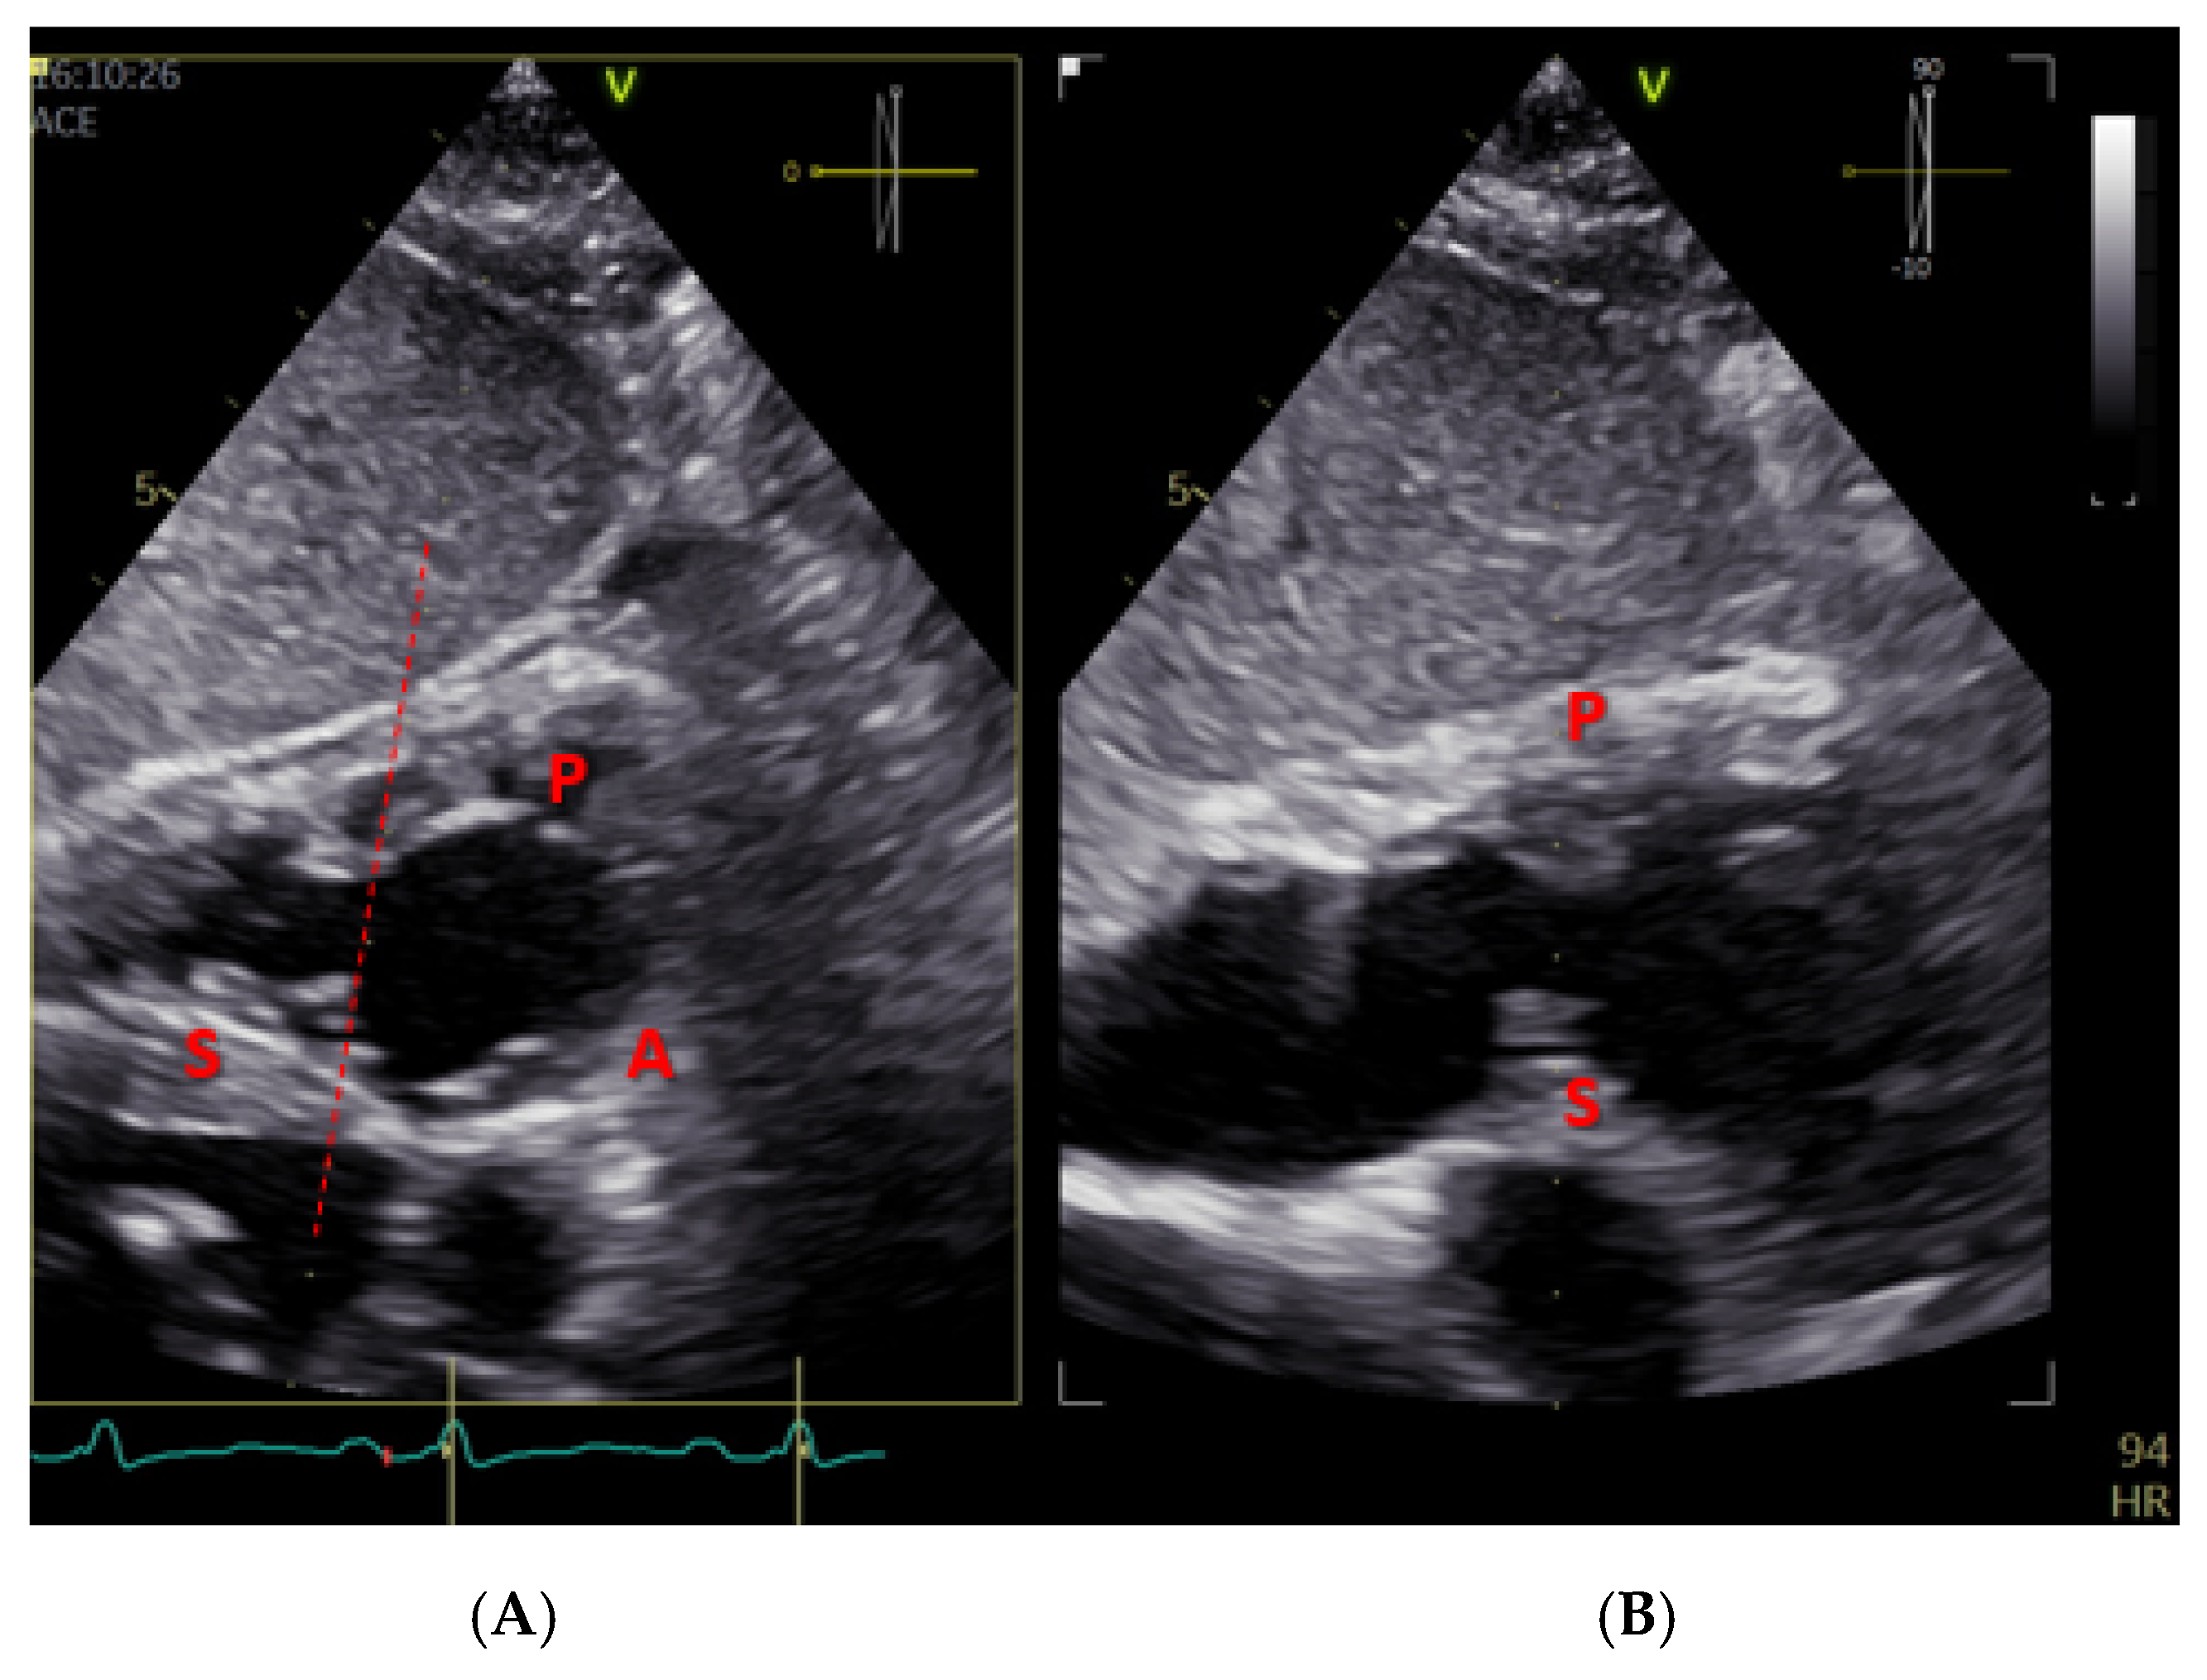

- Hahn, R.T.; Weckbach, L.T.; Noack, T.; Hamid, N.; Kitamura, M.; Bae, R.; Lurz, P.; Kodali, S.K.; Sorajja, P.; Hausleiter, J.; et al. Proposal for a Standard Echocardiographic Tricuspid Valve Nomenclature. JACC Cardiovasc. Imaging 2021, 14, 1299–1305. [Google Scholar] [CrossRef]